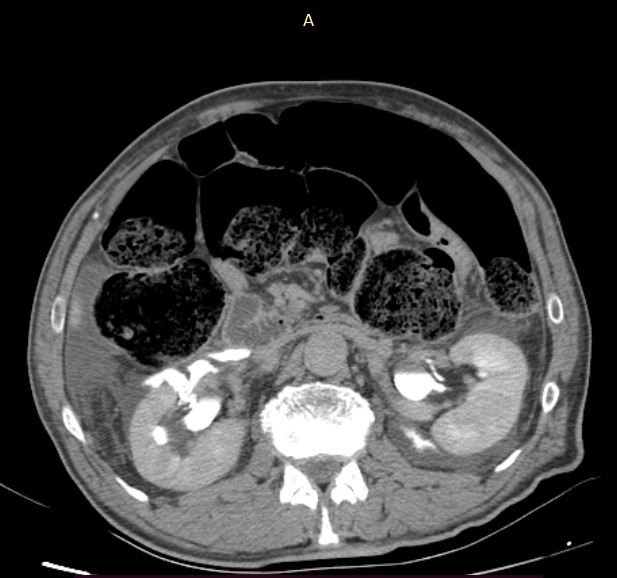

Figure 4. The exact location of the lesions of the renal pelvis and the contrast media leakage bilaterally.